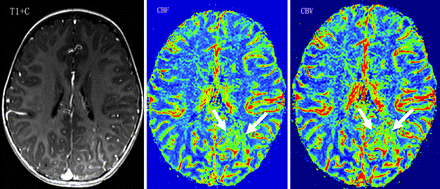

A 2-year-old girl with normal cognitive development (IQ = 105) and no seizures. Contrast-enhanced T1WI (T1+C) shows leptomeningeal enhancement in the left occipital lobe. PWI demonstrates increased WM rCBF and rCBV (CBF-AI = 0.26, CBV-AI = 0.24) in the involved region (arrows).

In the SWS group, CBF-AIs varied between −0.82 and +0.39, whereas CBV-AIs varied between −0.67 and +0.69. All CBF-AIs values were considerably outside the normal range (the smallest AI was −0.12, consistent with a 12% asymmetry), and patients were divided into 2 subgroups according to their CBF-AIs values: an rLP group (negative CBF-AIs, indicating abnormally low perfusion on the angioma side; n = 9; Fig 1) and an rHP group (positive CBF-AIs, increased perfusion on the angioma side; n = 5; Fig 2). Detailed results are listed in On-line Table 2. It should be noted that 4 of the 5 children with high perfusion had a history of seizures, but all 4 were free of clinical seizures for at least 4 months before the MR imaging scan.